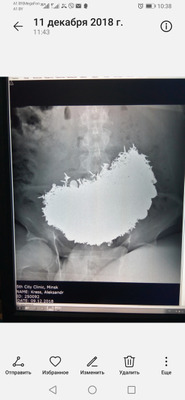

«Снимок „беременной“ самки питона»

Зачем же вы беременную рентгеном облучаете?